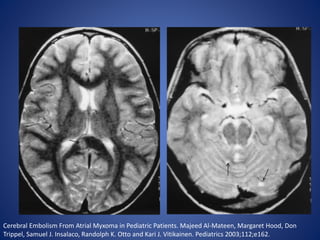

Cerebral Embolism From Atrial Myxoma in Pediatric Patients. Majeed Al-Mateen, Margaret Hood, Don

Trippel, Samuel J. Insalaco, Randolph K. Otto and Kari J. Vitikainen. Pediatrics 2003;112;e162.